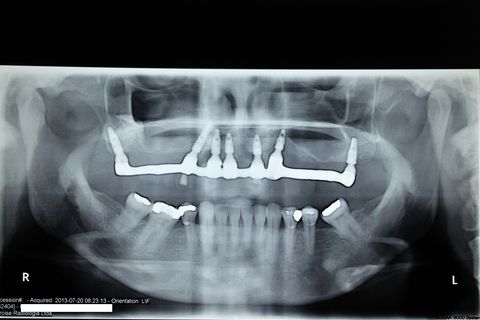

Controle Radiográfico 2015, após tratamento ortodôntico e nova prótese instalada. Nível ósseo mantido de forma bastante saudável. Implantes cone morse.

Paciente desdentada total superior, portadora de prótese total mal adaptada. Proposto para ela a instalação de 7 implantes, dos quais 5 na porção mais anterior da maxila(abordagem palatina). Foram instalados ainda dois implantes na junção pterigopalatina para eliminação de um possível cantilever produzido por enxertos de seios. O implante do lado direito precisou ser executado através de uma técnica transinusal devido ao resíduo insuficiente da tuberosidade. Nessa técnica, o trajeto entre a inserção cristal do implante e sua chegada ao pterigoide é feita levantando-se a membrana do seio maxilar e preenchendo-a com enxerto alógeno(bio-oss, no caso), sua ancoragem tem torque de inserção alto devido à densidade da junção - tal qual a técnica direta, utilizada no lado esquerdo

Foi sugerido à paciente tratamento ortodontico da arcada inferior.Ao final desse tratamento, foi confeccionada uma nova prótese fixa com dentes Heraeus Kulzer Premium, nova curva de spee e melhor relação com o corredor bucal.

Follow up de 4 anos.